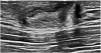

Common mammographic findings are subareolar ductal dilatation with intraductal calcified secretions, and coexistent mass-like opacities in subareolar location.4 The most commonly reported US findings of mammary duct ectasia include dilated ducts and tubular anechoic lesions that may contain echogenic debris within the subareolar region14 (Fig. 6).